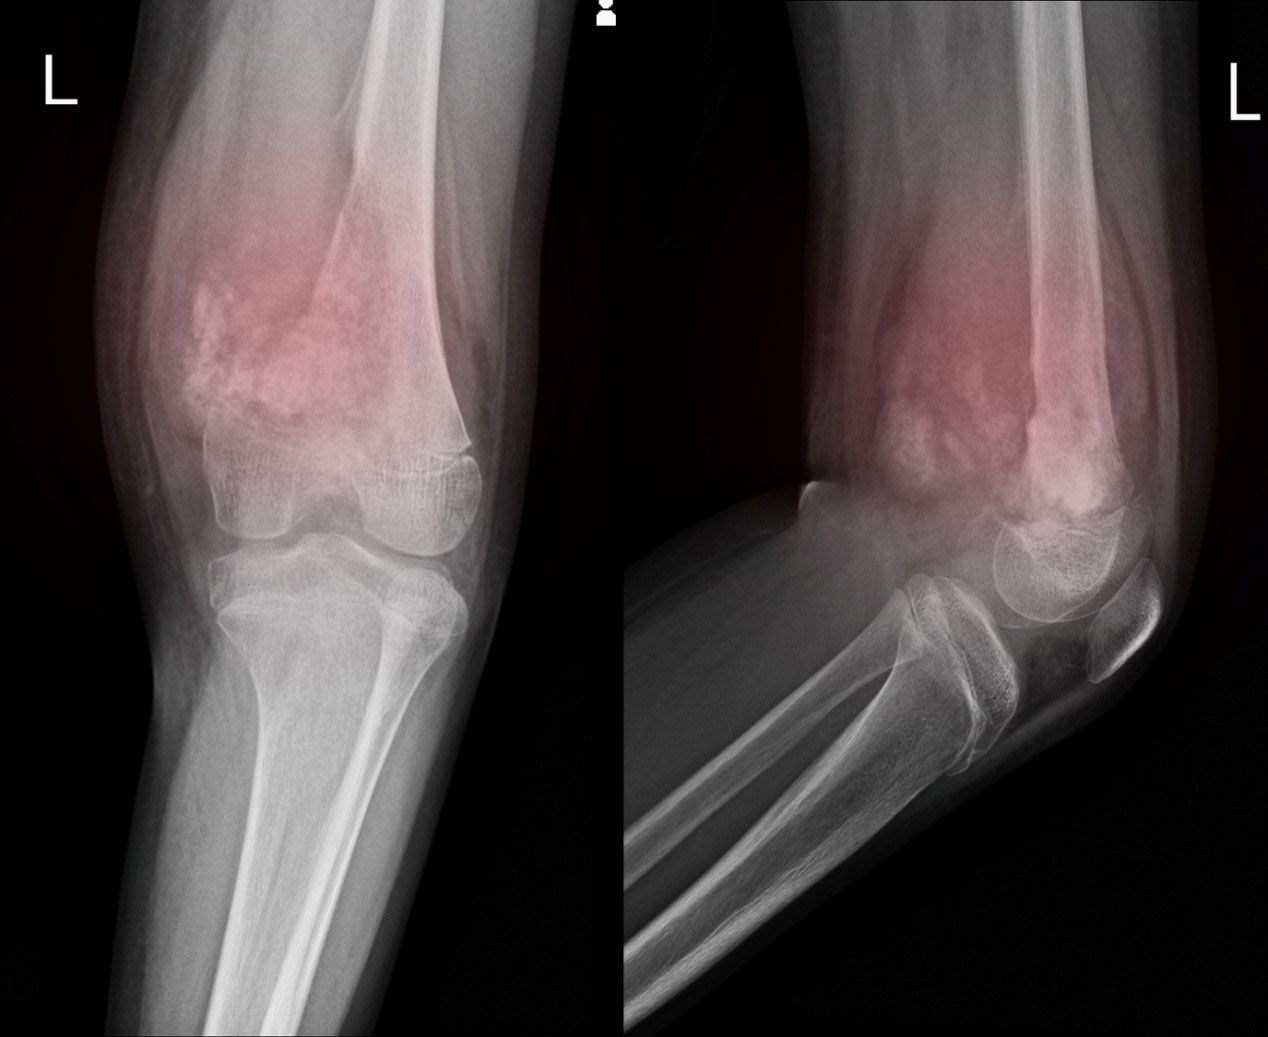

骨肉瘤(OS)是最常见的具有免疫抑制肿瘤微环境(TME)的恶性骨肿瘤。 采用辅助化疗和新辅助化疗治疗骨肉瘤,大大提高了骨肉瘤患者的生存期。 先前的一项研究表明,焦亡能显著诱导抗肿瘤反应并抑制肿瘤生长。许多细胞外刺激可以诱导癌细胞的焦变性,包括小分子抑制剂(BRAFi和MEKi),化疗药物(索拉非尼,洛铂和环己亚胺),以及CAR-T细胞释放的细胞溶解细胞因子。然而,复杂的机制和快速的清除限制了这些药物用于诱导焦亡。 成功诱导焦亡作为一种治疗策略仍然是一个挑战。

该团队合成了一种线粒体靶向聚合物胶束(OPDEA- PDCA),利用聚[2-(n -氧化物- n, n -二乙基氨基)甲基丙烯酸乙酯](OPDEA)靶向线粒体,并用共轭二氯乙酸(DCA)抑制丙酮酸脱氢酶激酶1 (PDHK1)。这种结合物通过启动线粒体氧化应激诱导焦亡。发现OPDEA-PDCA靶向线粒体,通过抑制PDHK1诱导线粒体氧化应激,导致骨肉瘤细胞系的免疫原性焦变性。此外,他们发现OPDEA-PDCA可以诱导可溶性程序性细胞死亡配体1 (PD-L1)分子的分泌。本研究提供了一种通过靶向调控线粒体启动焦亡的策略,有望与免疫治疗联合提高抗肿瘤疗效。